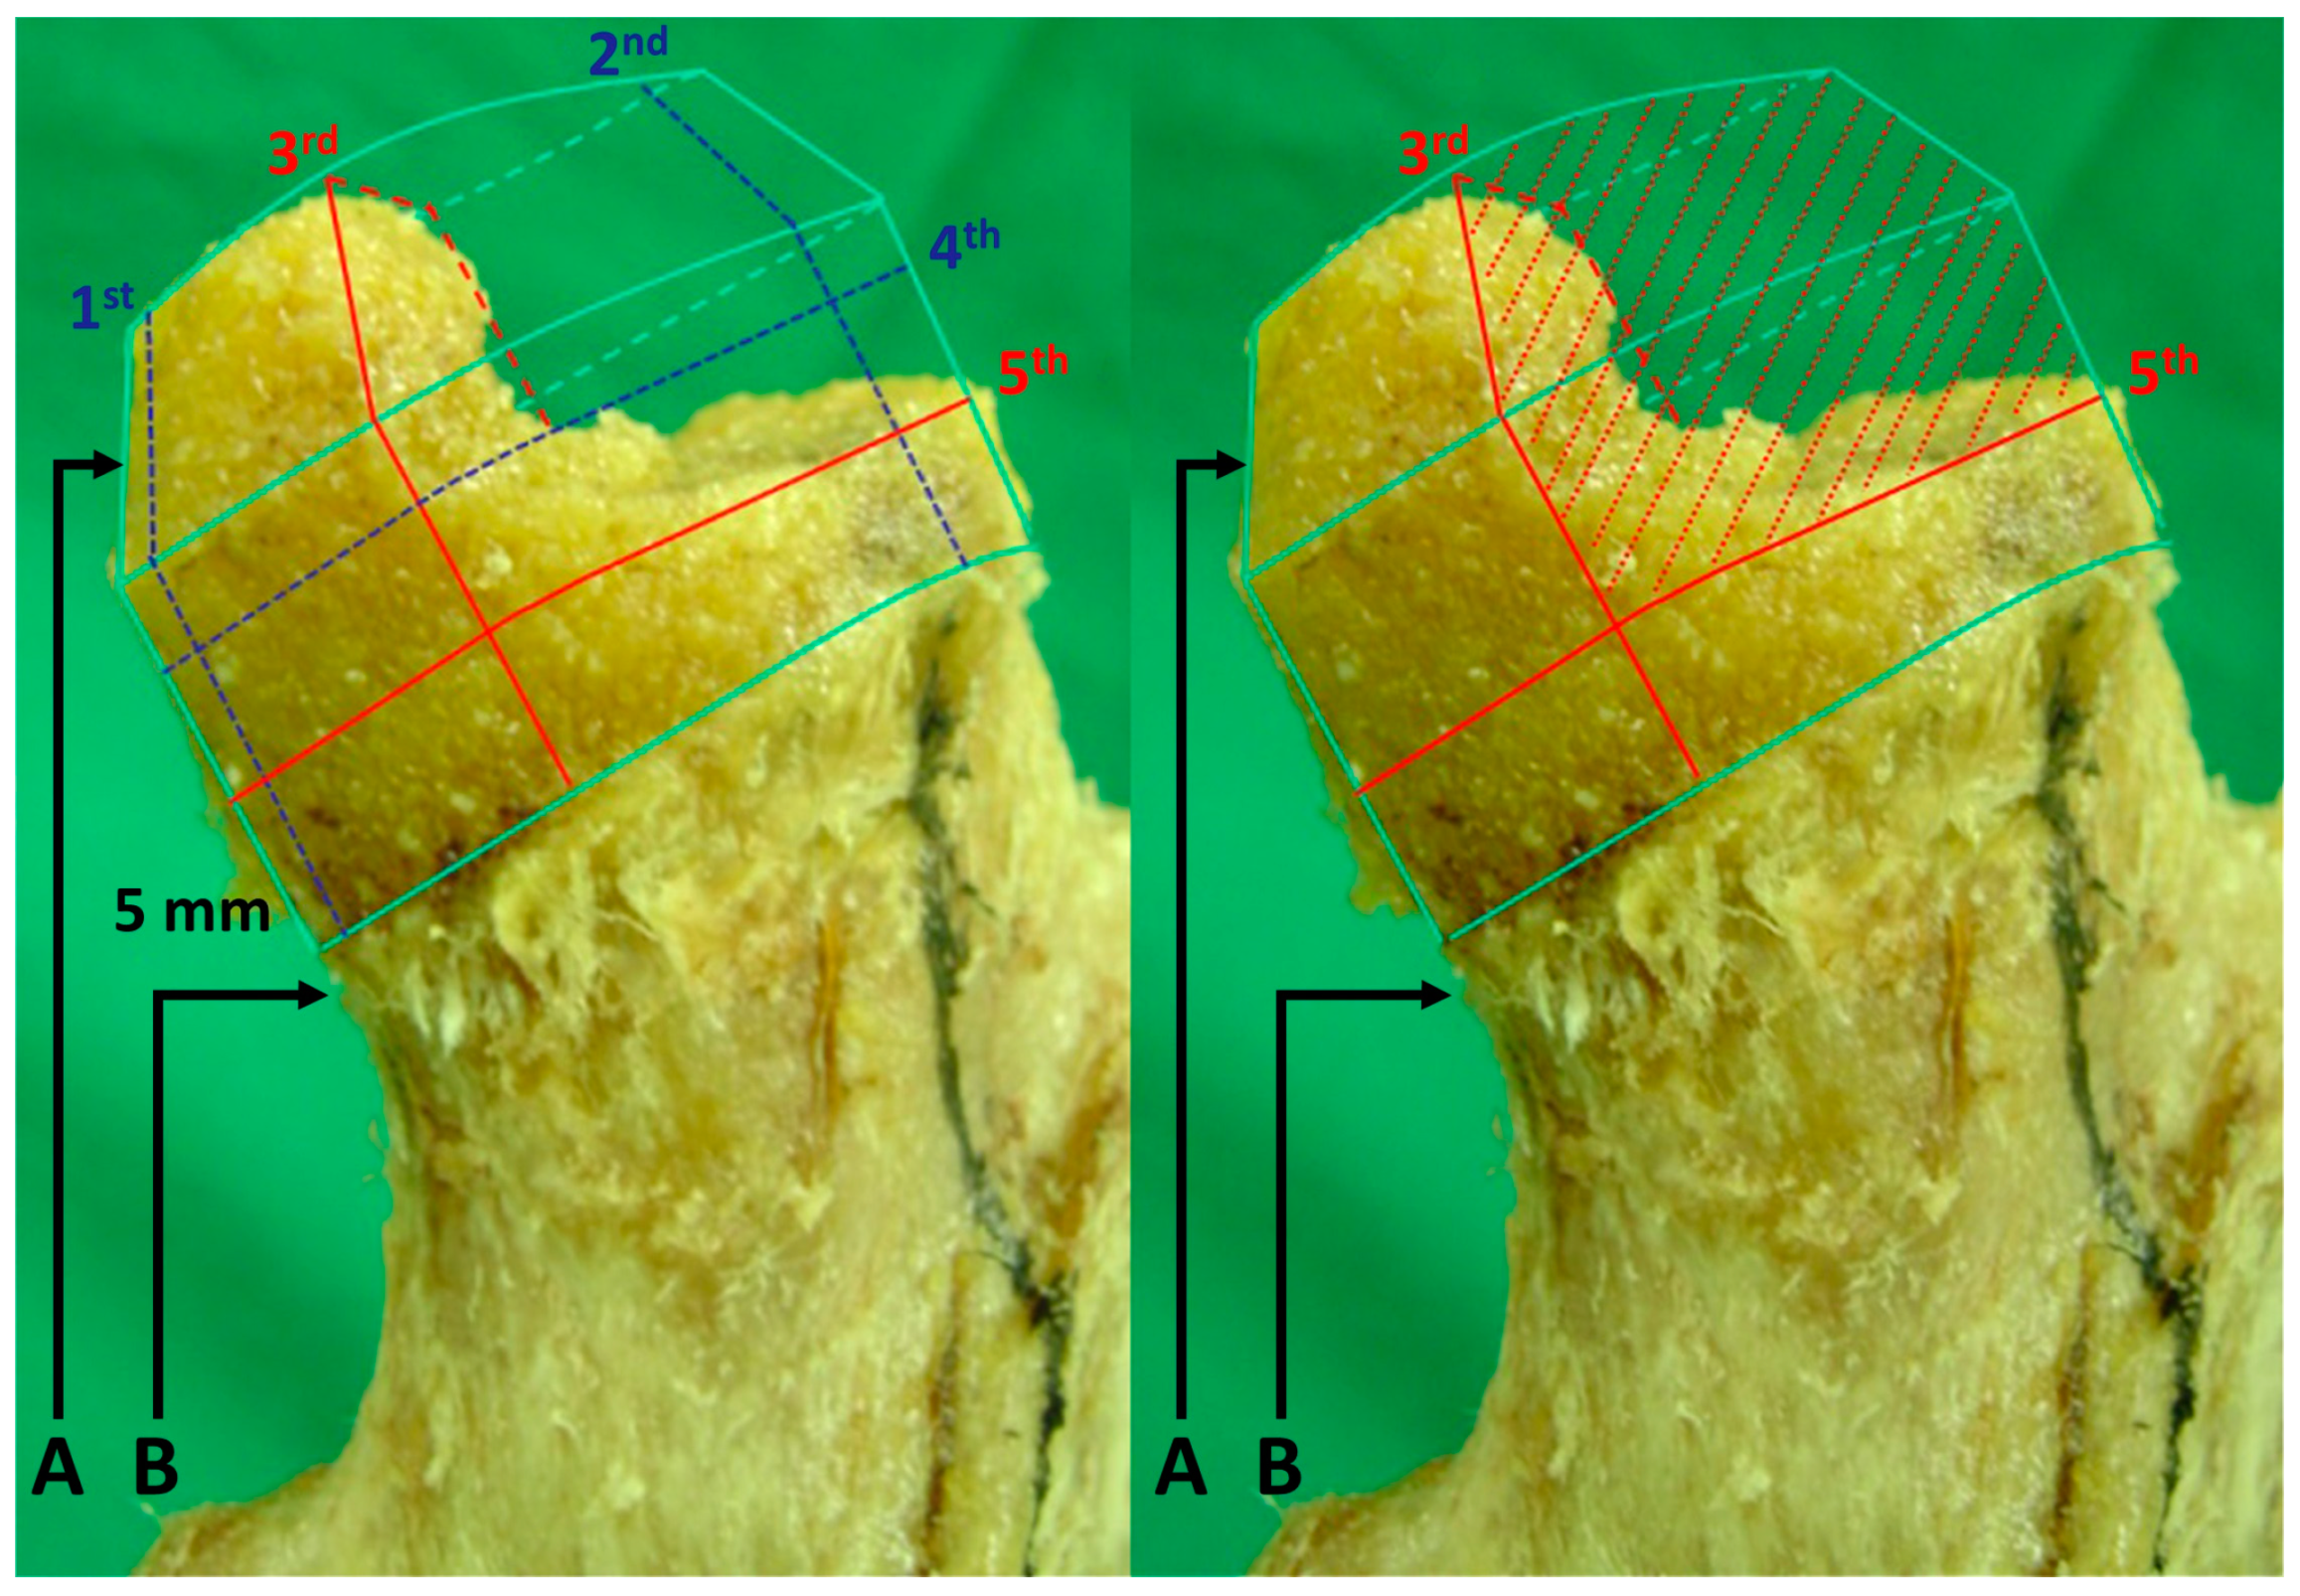

2.2. Creation of an Experimental Model of ONFH